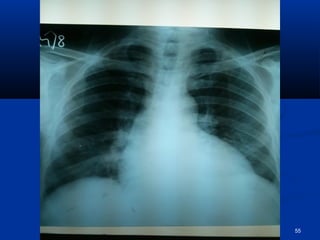

CCXXRR--PPAA

CCXXRR-PPAA .. FFiinnddiinnggss ooff ppuullmmoonnaarryy eeddeemmaa rreessoollvveedd 54

pprrooggrreessss  HHeeiiss aaffeebbrriillee && AAccttiivvee  SShhoorrttnneessss ooff bbrreeaatthh sseettttlleedd  RRtt.. SSiiddeedd WWeeaakknneessss iimmpprroovviinngg  LLeefftt ppoosstt.. ttiibbiiaall aarrtteerryy ggoott jjuusstt ppaallppaabbllee.. DDoorrssaalliiss ppeeddiissuuss nnoott ppaallppaabbllee yyeett.. ppaaiinn iinn lleegg iimmpprroovveedd.. lleevveell ooff ccoollddnneessss iinn lleefftt lleegg ddeeccrreeaasseedd ttoo lloowweerr 11//33rrdd RRFFTT’’ss ggoott bbaacckk ttoo nnoorrmmaall.. CCXXRR-PPAA .. FFiinnddiinnggss ooff ppuullmmoonnaarryy eeddeemmaa rreessoollvveedd 54